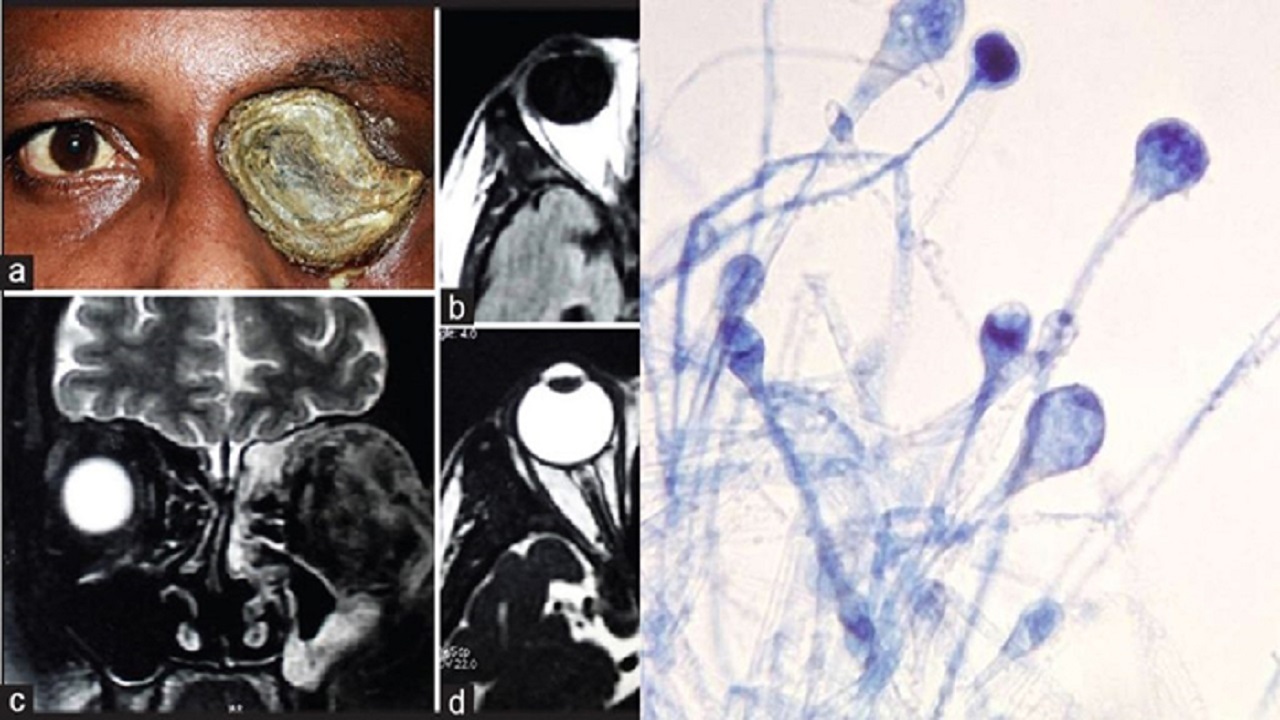

فوق تخصص نقص ایمنی درباره اصلیترین عامل گسترش قارچ سیاه مطرح کرد: این روزها هم به دلیل مصرف بی رویه و نابجای کورتن، بیماری قارچ سیاه در بعضی افراد مشاهده میشود. به طور معمول محل درگیری این بیماری، سینوسهای اطراف چشم و حفرههای داخلی آن است. البته قارچ سیاه در بعضی موارد میتواند با درگیری ریهها هم رو به رو شود. از اولین علائمی که بروز میکند میتوان به تغییر رنگ در محلهای درگیری از جمله رنگ تیره اشاره کرد.